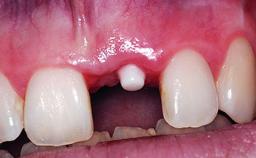

Replacement of a Failing Upper Right Central Incisor, Ridge Preservation and Late Placement of a NC Bone Level Implant

A 30-year-old patient presented at our clinic with a chief complaint of pain in her endodontically treated right maxillary central incisor (tooth 11) with a post-and-core and a fixed single crown. She had a very high lip line, a medium to thin soft-tissue phenotype, and a medium scalloped gingival contour. She also had high esthetic expectations because of her young age and beautiful smile. However, her expectations were realistic and she understood the risks of the treatment. At the initial clinical examination there was a slight mobility of tooth 11; no fistula was observed. The patient also had a single crown on the adjacent tooth 21. Both restorations were old and esthetically deficient. A digital periapical radiograph showed a very small periapical radiolucency, a thick intraradicular post, and no separation between root fragments.

Placement Protocol Early or late implant placement

Loading Protocol Conventional or early